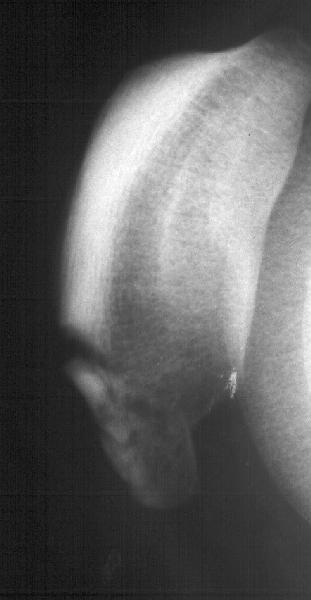

Мужчина 33 лет поступил через 2 недели после автоаварии (был за рулем) с переломом бедра. На этой же стороне есть перелом нижнего полюса надколенника. Клинически отека и гемартроза нет, интенсивная пальпация слабо болезненна прямо над линией перелома. Пальпаторно разгибательный аппарат сохранен. Бедро вчера синтезировано стержнем. Сделал сразу после этого снимок в полном сгибании - ничего никуда не расходится, и у меня рука не поднялась. Есть ли настоятельная необходимость оперативной фиксации, и если да, то чем?